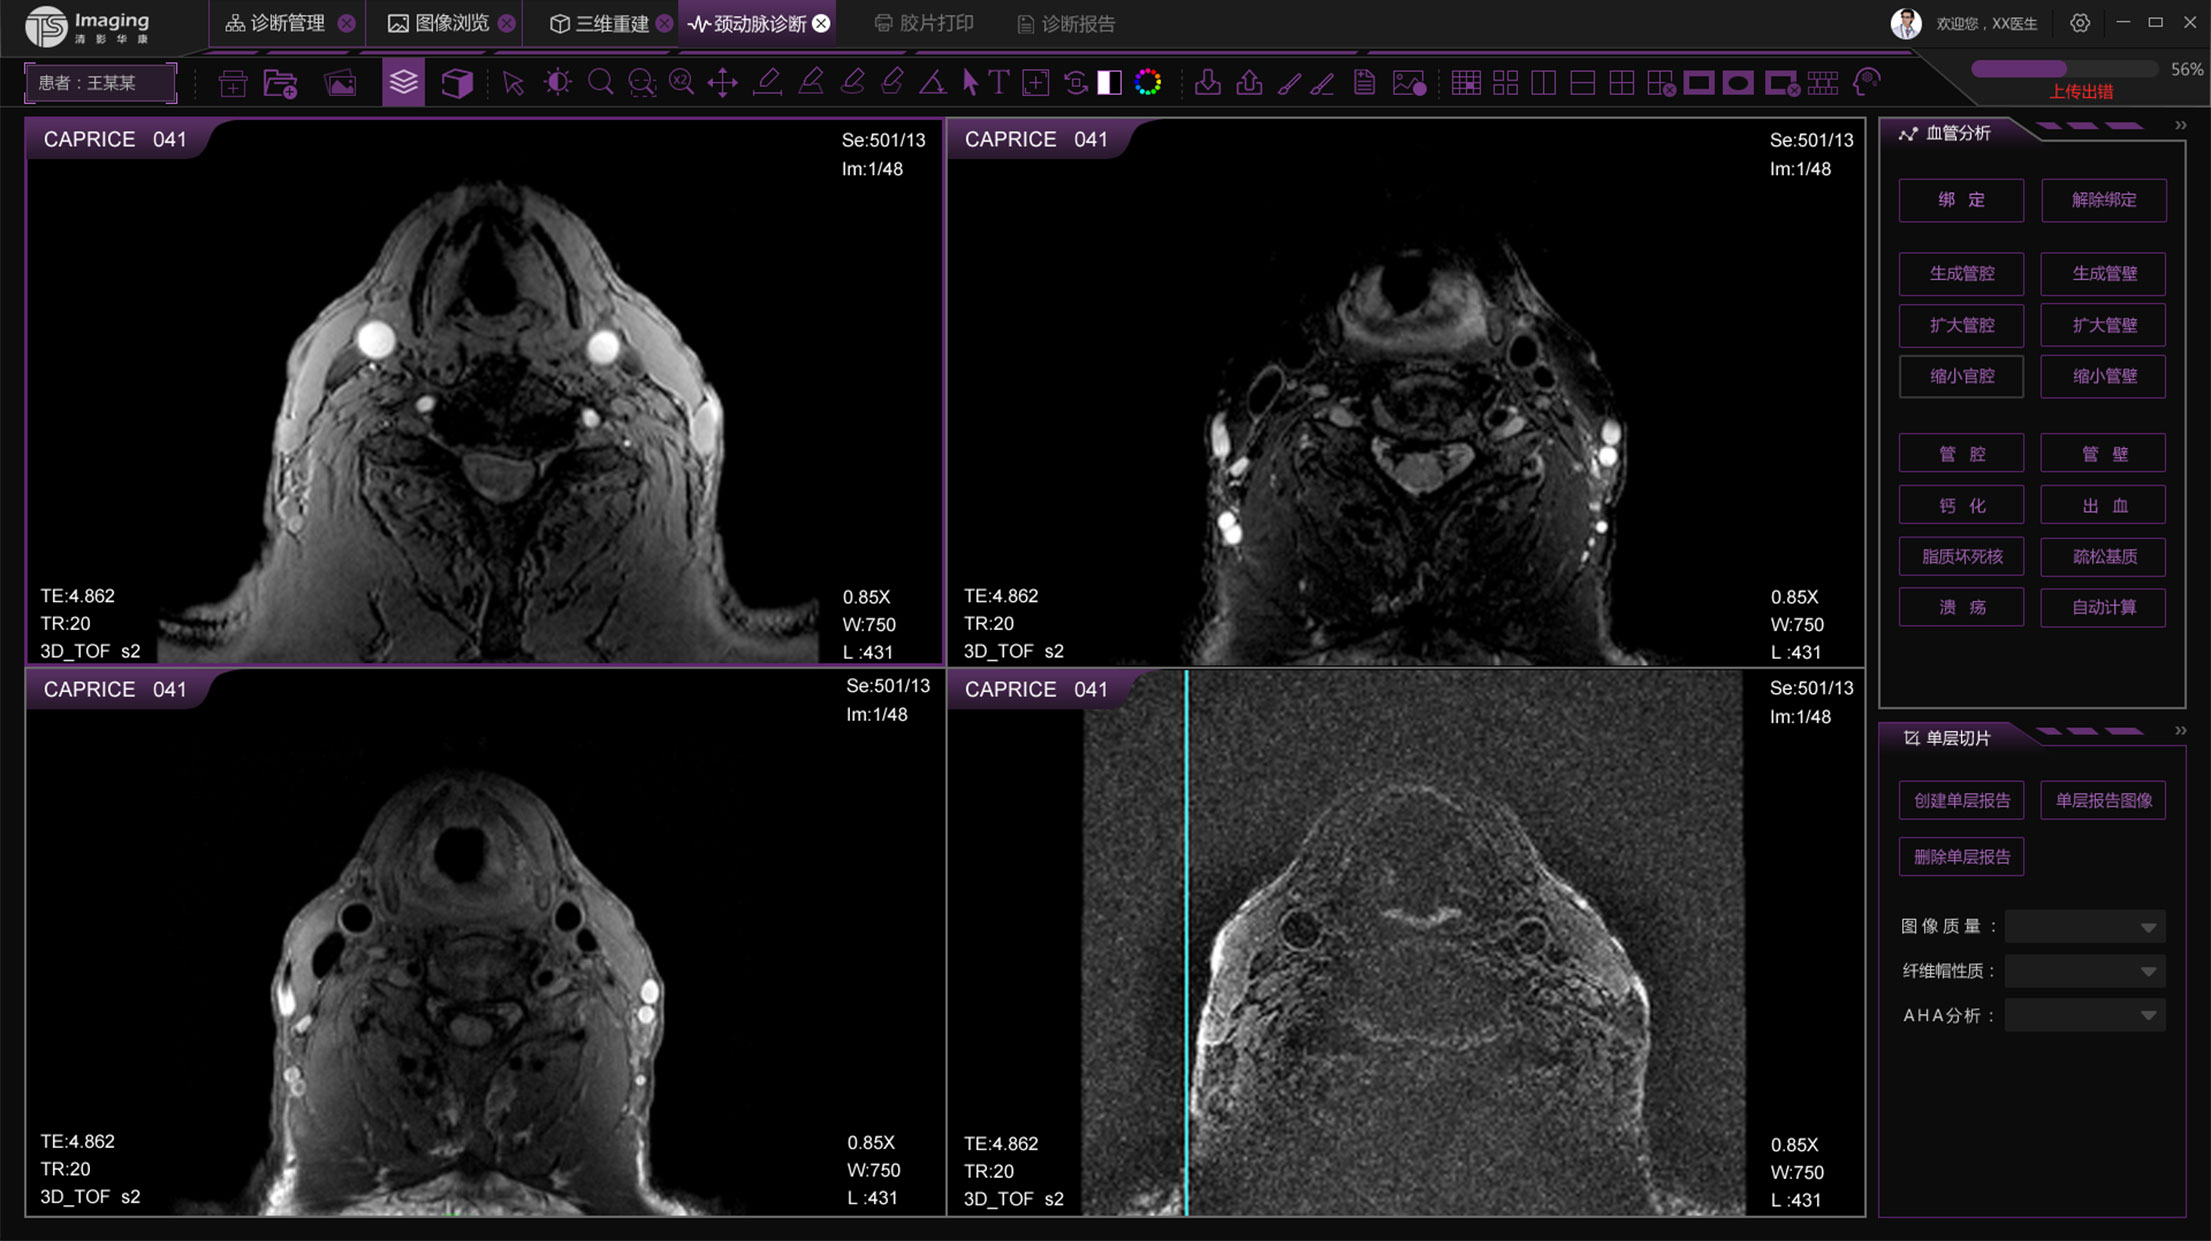

頸動脈診斷頁面

頸動脈診斷頁面整體布局和三維重建比較相似,最大的區別是右側的操作區域,血管分析都為按鍵操作,通過間隔的大小分成三部分。單層切片除了按鍵還有下拉菜單的操作。